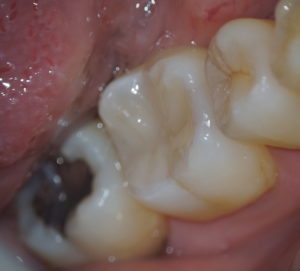

治療後

写真左:充填後の歯、写真右:治療中の歯